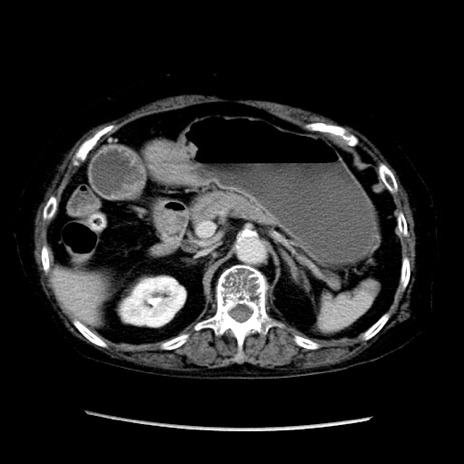

症例14(横断像)

【症例】 90歳代女性

【主訴】 腹痛・嘔吐

【現病歴】今朝から左側腹部痛を認めた。 経過観察していたが、嘔吐を認めたため来院。

【既往歴】 子宮癌術後

【身体所見】 意識清明、BP 127/54mmHg、P 98bpm Sp02 95%(RA)、BT 35.8°C、腹部平坦・軟腸ぜん動音聴取良好、右下腹部圧痛(+) 反跳痛なし

【データ】WBC 9800、CRP 0.46